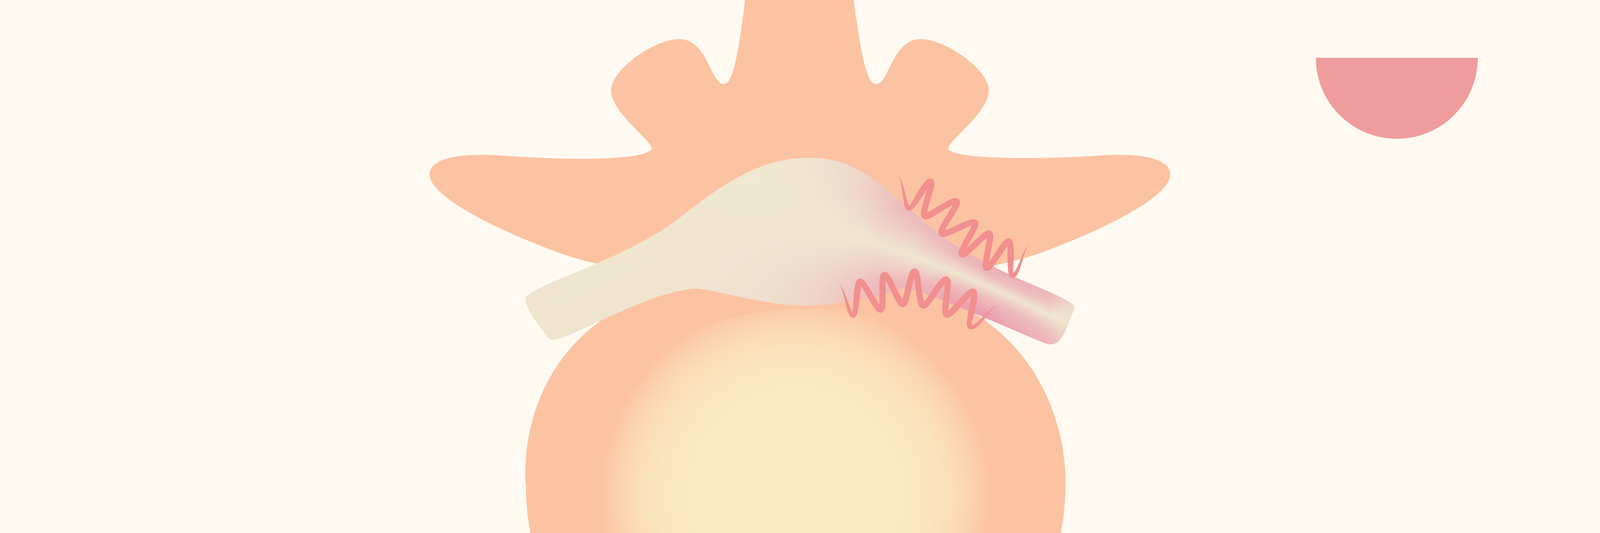

U heeft mogelijk al de diagnose gekregen, of u zoekt juist meer duidelijkheid over een hernia of wervelkanaalvernauwing (stenose) in uw rug of nek. Hieronder vindt u uitgebreide informatie vanuit meerdere perspectieven. Ook leest u wat een kijkoperatie in uw situatie kan betekenen.